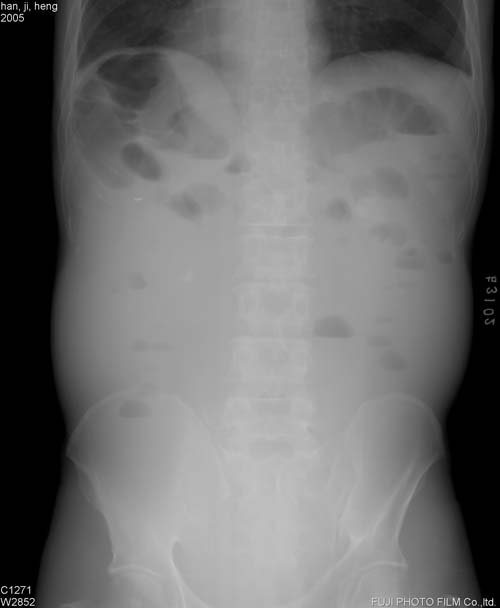

分析一下这个没有病史的腹平片.

片子放反了

可见多个短液平,小肠不全梗阻??

盆腔区域未见肠气影且双侧胁腹线模糊不清,结肠影上移,腹部多个短小气液平面,考虑腹膜炎腹水可能,建议做b-us检查

考虑小肠不全性梗阻。

小肠不全梗阻

片子放反了吧!没病史,考虑肠梗阻,急性胃肠炎

片子反了,见小肠内多个小液平面,考虑为小肠的不完全性梗阻.

可见多个高位短液平,考虑低位性肠梗阻.

腹部多个小液气平面,腹脂线不清,腹部膨隆:

不全性肠梗阻

若不是图片放反了,考虑病人内脏反位。

病人呈“蛙状腹”,双侧胁腹脂肪线模糊不清,肝三角消失,小肠内大量积液,可见多个小液平面。

考虑:腹腔积液,绞窄性肠梗阻不能排除,建议结合临床,超声进一步检查。

1.“蛙状腹”,肠曲内上移位,双侧胁腹脂肪线模糊不清_____系腹腔积液表现.

2.小肠扩张积液积气,以积液为主.没有卧位片,难以判断结肠情况(观察肠梗阻,应常规立卧位).

a.如结肠有积液积气,肠梗阻应该是麻痹性的,是腹膜刺激引起的 .

b.如结肠没有积液积气,当考虑小肠梗阻.

做个ct非常有助于诊断(常可查明梗阻原因)

腹部多个小液气平面,腹部膨隆,腹脂线不清,考虑1.低位性肠梗阻. 2.腹膜炎并腹水.